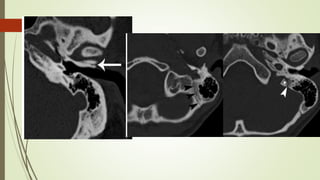

• #49 Izq: Sutura timpanoescamosa, hace mímica de frafctura Centro y derr. Sutura occipitomastoidea

• #50 IZQ: Sutura esfenoescamoosa,, lateral al foarmen espinoso(punta de flecha) DDER: sutura esfenopetrosa: foramen oval(astericos), trompa eustaqui (punat negra)

• #51 IZQ: Canal arqueado(petromastoideo) . Canal SC superior DER: Hiato del facial(blanca), ganglio geniculado (negra)